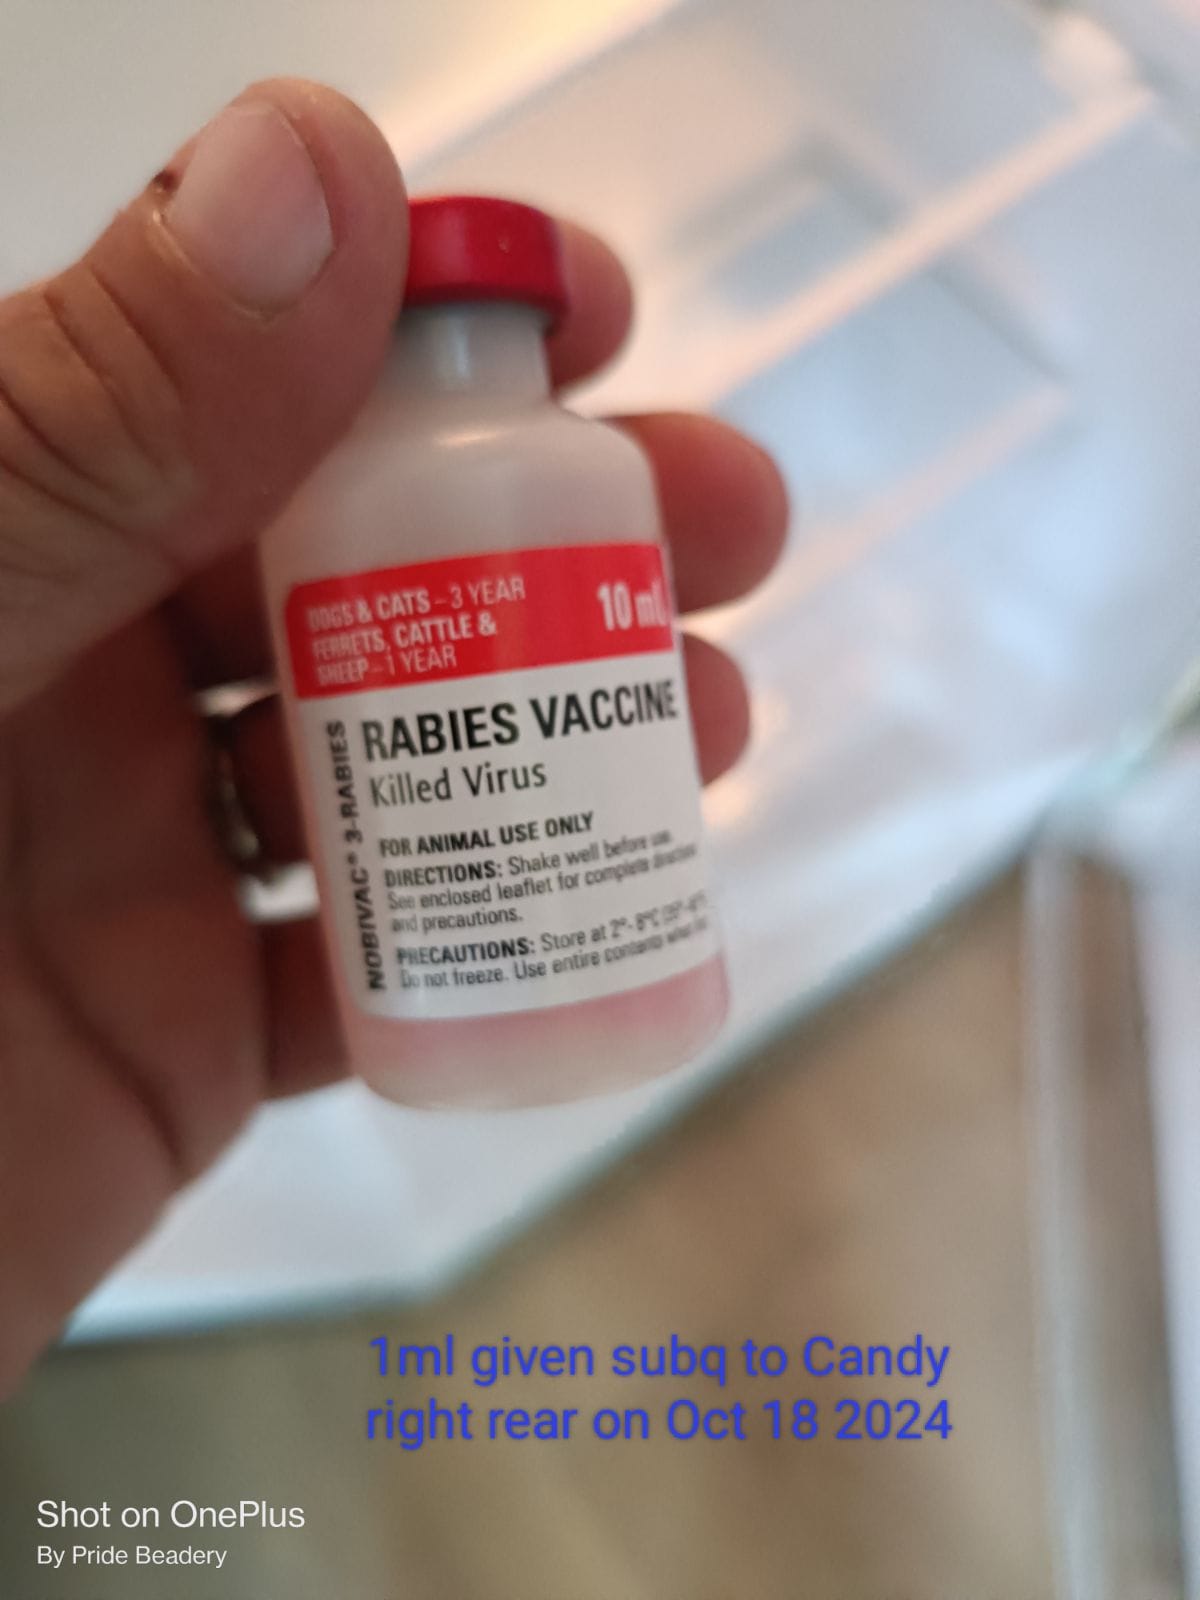

| Insert Date | Name | Dosage | Rabies file | Due Date |

| March 15, 2025 | Rabies - Rabies - IMRAB 3 TF | 1ML |

|

June 18, 2025 |